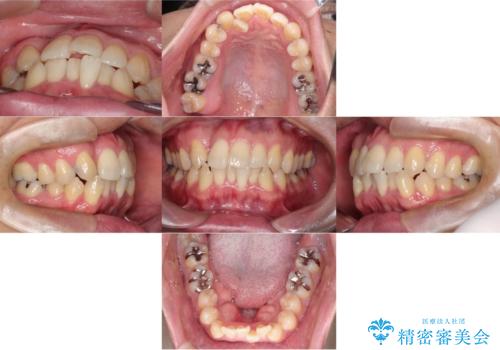

- 「歯のデコボコと前歯が引っ込んでいるのを治したい」を主訴に来院された患者様です。

デコボコの量が多かったため上下左右4を抜歯してワイヤー矯正で治療を行いました。

正面から見たときに右上2が全く見えないくらい、右上2が後ろに引っ込んでいる状態でしたが綺麗に並べる事が出来ました。

スムーズに治療を進める事ができ、2年2か月で治療をお終えました。

顔貌に対して歯の正中も合いました。